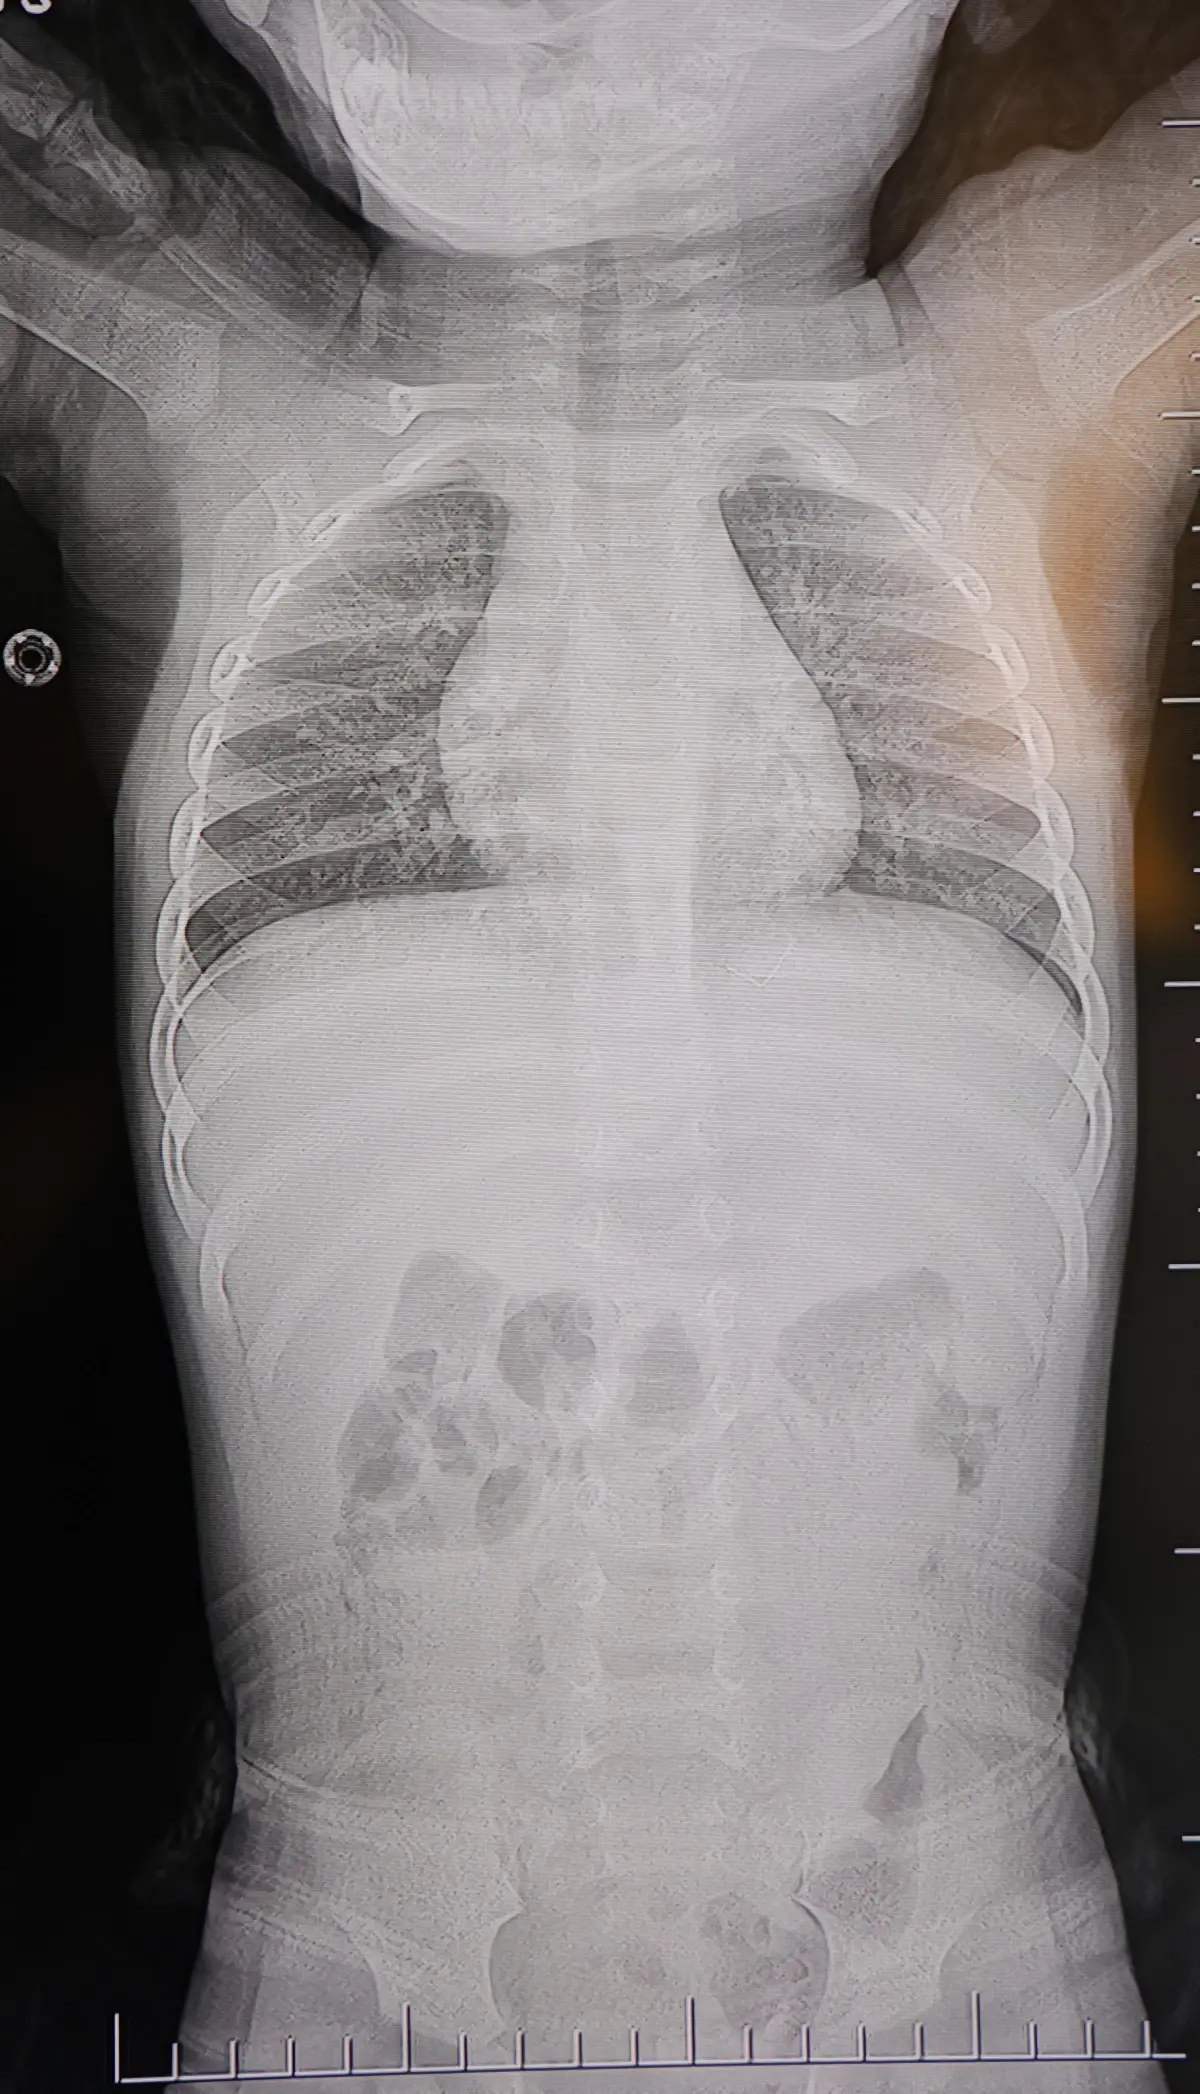

Kahramanmaraş'ta bir yaşındaki bebek, sırt üstü yatmak istemediği için hastaneye götürüldü ve sırtından akciğer zarına doğru ilerlemiş 2 cm uzunluğunda bir zımba teli çıkarıldı. Cerrahi müdahale lokal anestezi ve sedasyonla gerçekleştirildi.

Kahramanmaraş'ta bir yaşındaki bir bebek, sırt üstü yatmak istemediği ve sürekli ağlaması nedeniyle ailesi tarafından hastaneye yönlendirildi. Yapılan detaylı muayeneler sonucunda, bebeğin sırt bölgesinden akciğer zarına doğru ilerlemiş 2 cm uzunluğunda bir zımba teli tespit edildi.

İlgili aile, bebeğin rahatsızlığını farklı kliniklerde değerlendirdikten sonra HG Hospital'e başvurdu. Prof. Dr. İdris Altun ve ekibi, görüntüleme tetkikleriyle zımba telinin konumunu kesin olarak belirledi.

- Ultrason ve röntgen ile telin konumu tespit edildi.